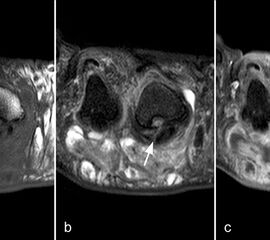

Die sagittalen PD FS Schichten im medialen und lateralen Bereich der plantaren Platte (a, c) zeigen eine völlig unauffällige,  Der kleine Flüssigkeitseinschluss in der Mittellinie der Zehe (b, Pfeil) entspricht einem physiolo

Abbildung 9

Zwischen der plantaren Platte und der Grundphalanx ist in der Mittellinie des Gelenkes ein kleiner Rezessus vorhanden (Abb. 9).

Dieser flüssigkeitsgefüllte Raum darf nicht als Ruptur der plantaren Platte fehlinterpretiert werden 23. Verletzungen der plantaren Platte erfassen immer auch den medialen oder lateralen Zügel.